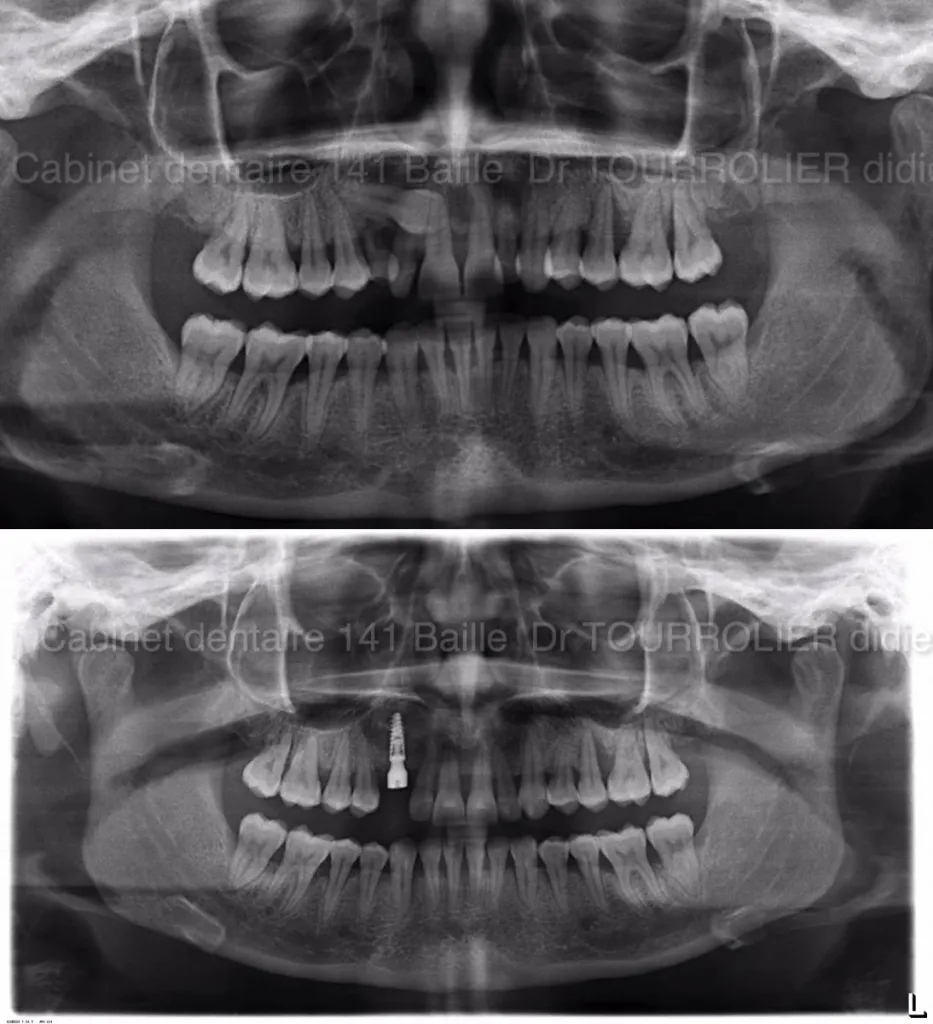

Traitement d'une canine INCLUSE ectopique par IMPLANTATION Immédiate

Dans certaines situations  ,les canines incluses ne peuvent pas être dégagées chirurgicalement et ne peuvent être tractées sur l'arcade par un moyen orthodontique.La solution idéale est alors d'extraire cette canine incluse et de la remplacer par un Implant avec une technique d'implantation immédi...